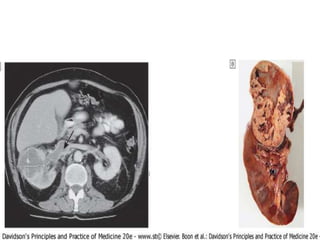

Computed tomography (CT)

• CT is particularly useful for characterising mass lesions within the

kidney , or combinations of cysts with masses. It gives clear definition

of retroperitoneal anatomy regardless of obesity.

• New developments in spiral CT enable three-dimensional

arteriograms to be obtained. This produces high-quality images of the

main renal vessels and is of value in trauma, renal haemorrhage and

the investigation of possible renal artery stenosis. The speed of image

acquisition also enables functional assessment and enhancement of

vascular structures, e.g. angiomyolipomas.

• CT is also useful for demonstrating renal stones, and in many centres

CT urography is replacing IVU as the first radiological investigation for

renal colic. However, there are risks of exposure to contrast medium .

chronic obstruction to urinary outflow.